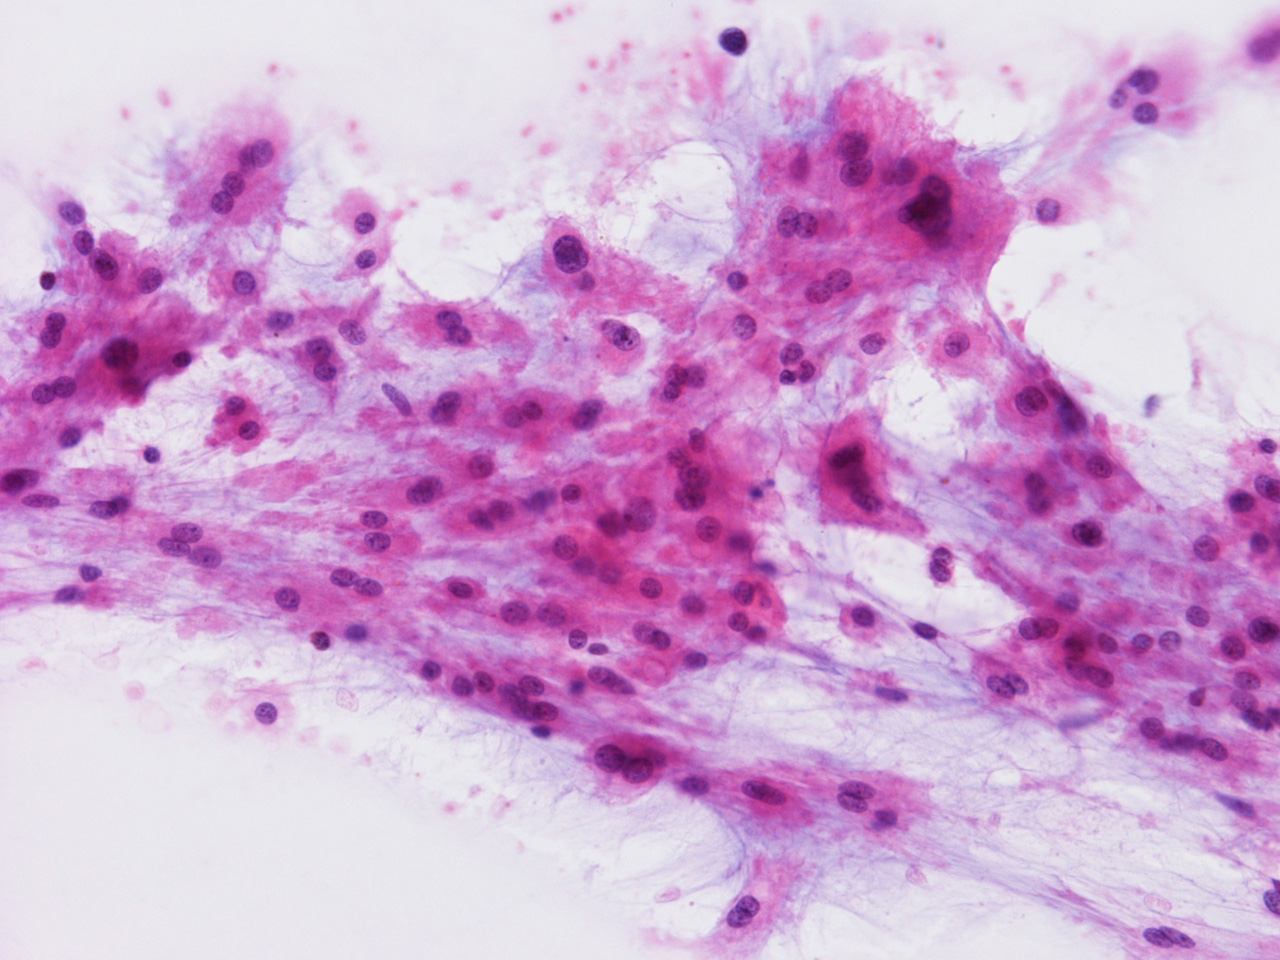

At the time of operation, a cytologic squash preparation (H&E) was prepared (Panels BC, and D). On low magnification, the lesion is composed of large clusters of eosinophilic cells with centrally located nuclei. There is some bluish acellular substance admixed with the tumor cells (Panel B). If you pay attention, some of the cells are arranged in short chains (arrows in Panel C). This is a frequently seen phenomenon in chordoma. On high magnification, the cells have centrally located medium sized to large, hyperchromatic nuclei. The cytoplasm is finely eosinophilic but not particularly bubbly  (Panel D). The frozen sections (Panels E and Freflect the cytologic features. The tumor is composed of solid sheets of large tumor cells admixed with small amount of fibrous areas, mild chronic inflammatory cell infiltration and hemosiderin depositions (Panel E). On high magnification, the tumor cells are admixed with bluish extracellular material.  The cytoplasm is coarsely granular with fine bubbles. The permanent sections (Panel G and Hshow similar features. And the bubbly cytoplasm is more prominent in the permanent sections (Panel H). Focal bone invasion is present (Panel I). The cytoplasmic vacuoles are best appreciated in the semithin section (Panel M). Results of special studies are as follows:

The characteristic histologic findings in chordomas are large polygonal cells with distinct cell membrane and the vacuolated physaliphorous cytoplasm, the term deriving from the Greek physalis, or "bubble. The vacuolated or physaliphorous cells are best appreciated in cytologic smears or squash preparations. Tumor cells grow in small nests and cords within a myxoid/chondroid matrix and demonstrate round, sometimes rather uniform nuclei with low nuclear-to-cytoplasmic ratios. The tumor cells tend to adhere into clusters and cords. The classic large physaliphorous cell has a centrally located nucleus surrounded by a narrow rim of cytoplasm that in turn, is encircled by a ring of more peripherally located cytoplasmic vacuoles. Nuclear grade is not particularly high in some cases but many of them have clearly recognizable nuclear pleomorphism. Occasional large, atypical cells are present. These nuclear changes should not be present in benign notochordal cell tumor and ecchordosis physaliphora/fetal vestige [Amer & Hameed, 2010]

On cytologic smears [Crapanzano JP et al., 2001], chordoma cells tend to be cohesive but not as cohesive to each other as carcinomas. Strings of chordomas are common features.